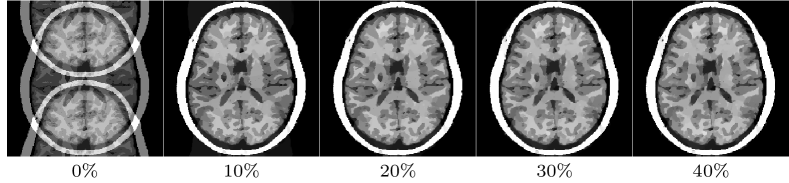

The advantage of ICB over LPLS is easily explained by the weighting between channels. While LPLS always relies on a 50/50 weighting, the result for ICB has been obtained with an MR influence of . For further comparison to a 50/50 weighting (and the overall influence of the channel weighting) we provide a weighting series in Figure 7.

We further comment on the channel weighting, i.e. the parameters and . As already mentioned in the previous section, a known drawback of joint reconstruction methods is a cross-talk between the different channels, i.e. channels might cause artifacts in other channels. This can e.g. be the transfer of a structure from one channel to the other (cf. the PET image in Fig. 11), or the smoothing out of structures since they are not present in all channels (cf. the lesion in the PET image in Fig. 9). This is an issue which is hard to avoid. However, the weighting between channels, i.e. the parameters and can indicate, which structures are likely to be artifacts or falsely influenced by the joint reconstruction. Figure 7 shows the PET reconstruction with an increasing amount of influence of the MR channel. In comparison to a seperate reconstruction (upper left), already an influence of 10 percent of the MR image substantially sharpens the PET image. This trend continues as the influence further increases. Unfortunately, the hot lesion in the upper right part of the PET image starts to be smoothed out with increasing MR weighting. This error, however, can be identified by a look at the seperate reconstruction and low MR weightings.